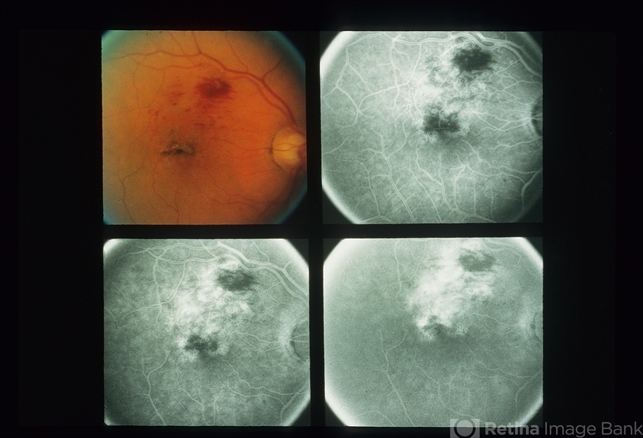

- Branch Vein Occlusion

- Condition/keywords

- branch vein occlusion (BVO)

- Eighty one year old white female, right eye 20/100, left eye 20/20.